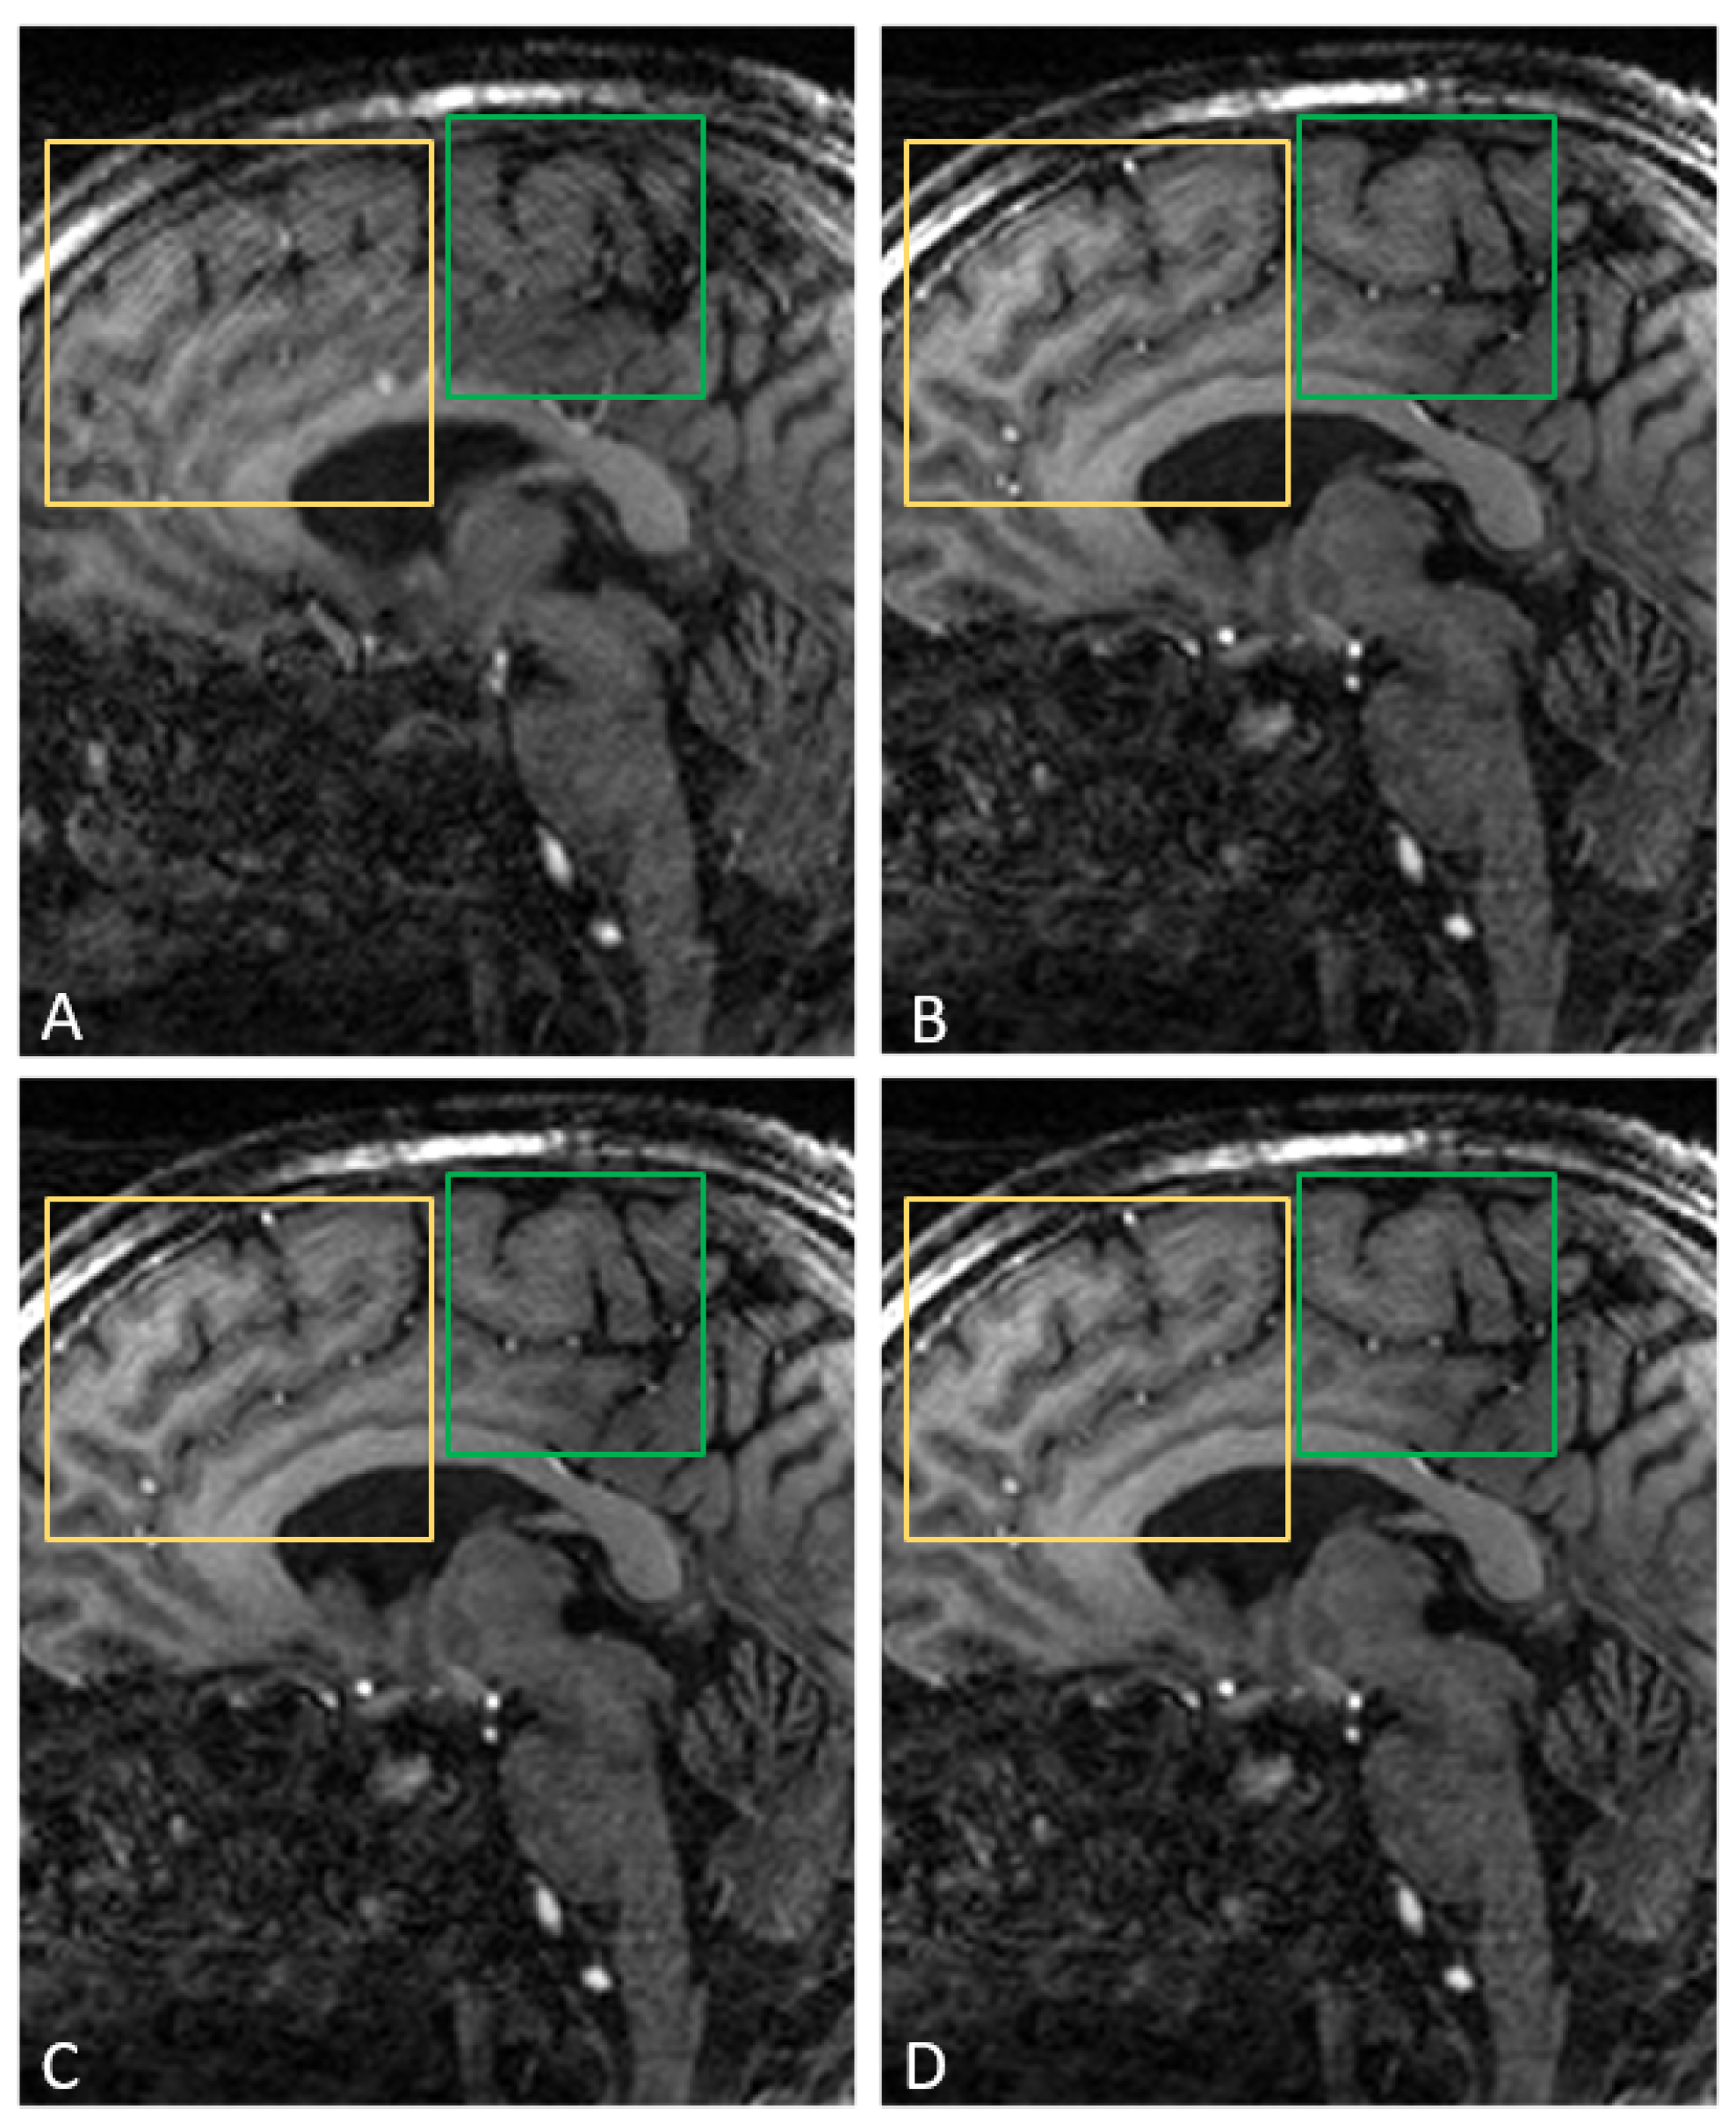

- Mugler, J.P., III; Brookeman, J.R. Three-dimensional magnetization-prepared rapid gradient-echo imaging (3D MP RAGE). Magn. Reson. Med. 1990, 15, 152–157. [Google Scholar] [CrossRef] [PubMed]

- Cordero-Grande, L.; Ferrazzi, G.; Teixeira, R.P.A.G.; O’Muircheartaigh, J.; Price, A.N.; Hajnal, J.V. Motion-corrected MRI with DISORDER: Distributed and incoherent sample orders for reconstruction deblurring using encoding redundancy. Magn. Reson. Med. 2020, 84, 713–726. [Google Scholar] [CrossRef] [PubMed]